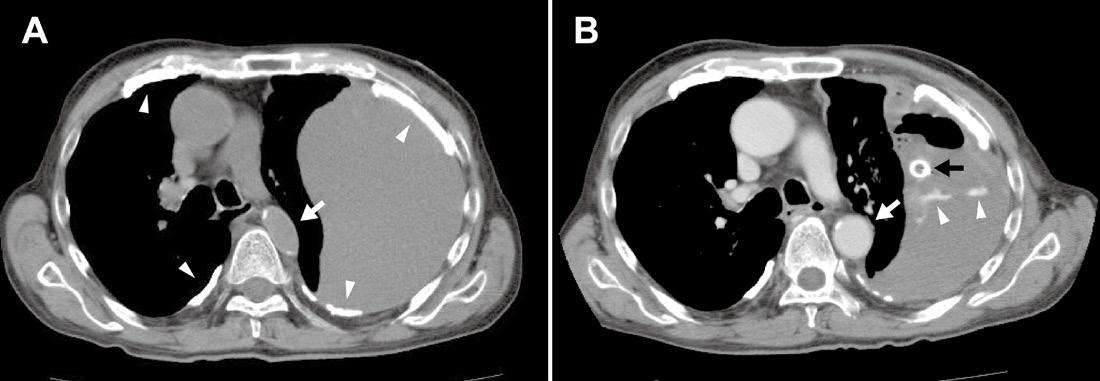

Upon closer inspection, parasternal long-axis view revealed a ventricular septal defect with an overriding aorta and RVH concerning for TOF (Image 2). Parasternal shortaxis cardiac view redemonstrated RVH with interventricular septal flattening indicative of right ventricular pressure

Image 2. Parasternal long-axis view of the heart highlighting the findings of a ventricular septal defect (*) with an overriding aorta (Ao) and right ventricular hypertrophy (arrow). LA indicates left atrium; LV, left ventricle; RV, right ventricle.

Treatment was shifted from a focus on sepsis to TOF management. Additional IVF hydration was limited, and the patient was started on propanolol for rate control. Due to the patient’s age, the decision was made to not administer prostaglandins as he was likely not ductus dependent. He was found to improve after these interventions. Cardiology was consulted, and despite not identifying physical exam findings concerning for TOF such as skin discoloration signifying cyanosis, or a systolic thrill and ejection murmur at the left sternal border, once they were shown the POCUS images cardiology consult initiated procedures for referral to the National Institute of Cardiovascular Diseases in Lima for definitive surgical treatment. Four days later a comprehensive echocardiogram confirmed the diagnosis of TOF.

Image 3. Parasternal short-axis view of the heart notable for interventricular septal flattening (*) due to right ventricular pressure overload in the setting of right ventricular hypertrophy (arrow). LV, left ventricle; RV, right ventricle.